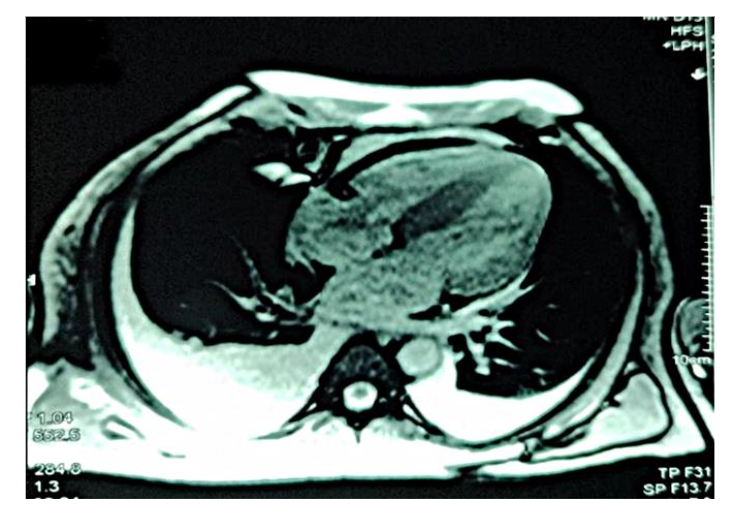

Figure 3: Diffuse global late gadolinium enhancement observed on cardiac magnetic resonance imaging.

Figure 3 depicts diffuse global late gadolinium enhancement observed on cardiac magnetic resonance imaging.

Cardiac MRI is a pivotal tool for detecting early amyloid deposition, particularly in patients with inconclusive echocardiographic findings. The capacity of cardiac MRI to identify diffuse late gadolinium enhancement provides invaluable insight into disease severity and extent of myocardial involvement. In this case, a comprehensive diagnostic approach confirmed amyloid light-chain cardiac amyloidosis through elevated lambda-free light chains, a low kappa/lambda ratio, and evidence of plasma cell dyscrasia from bone marrow biopsy. The absence of myocardial uptake on Tc-99m pyrophosphate scintigraphy excluded transthyretin cardiac amyloidosis, further solidifying the diagnosis.